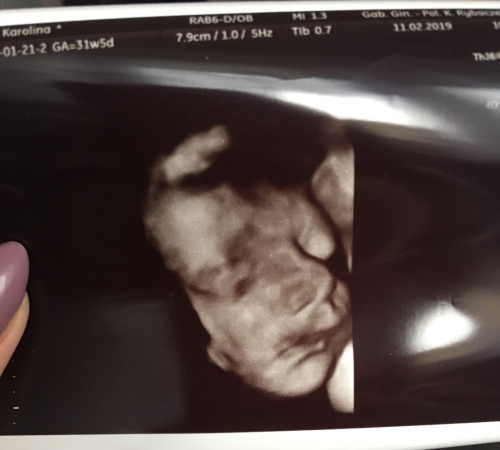

Już Wam opowiadam, Marcelina ma się dobrze! Wszystkie wymiary są jak najbardziej w normie, gin mówiła że absolutnie nie ma się do czego przyczepić, tętno 151, waży 1904g!

Wiecie co ? Ginekolog robi nam to badanie a po chwili takie zdziwienie na jej twarzy, trochę się wystraszyłam a ona mówi „Matko! Ile to dziecko ma włosów na głowie!”

P.S. Zapytałam czy dalej jest dziewczynką, więc pokazała nam ładną, dorodną pipcię